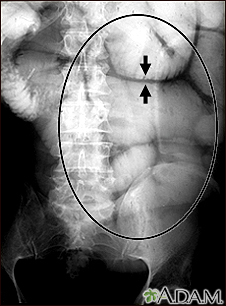

Ileus - x-ray of bowel distensionBackIleus - x-ray of bowel distensionThis abdominal x-ray shows thickening of the bowel wall and swelling (distention) caused by a blockage (pseudo-obstruction) in the intestines. A solution containing a dye (barium), which is visible on X-ray, was swallowed by the patient (the procedure is known as an upper GI series). E-mail FormEmail ResultsName:Email address:Recipients Name:Recipients address:Message: